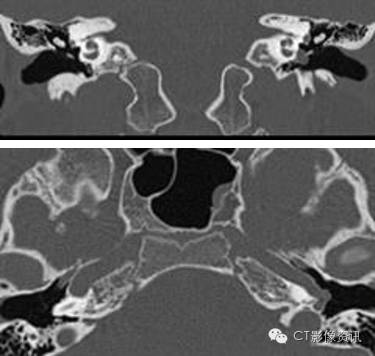

病史 10岁男孩,左侧耳聋(传导性耳聋为主)。无疼痛或者耳鸣症状。耳镜可见该患者后鼓室内有一紫色肿块并伴随鼓膜活动性下降。患者否认其它病史及肿瘤、耳聋家族史。

1.左侧卵圆孔异常?(单选)

2.上图所见提示左侧脑膜中动脉缺如?(单选)

3.左侧颈内动脉所见说明什么?(单选) 异常走行起源于颈内动脉 异常走行起源于颈外动脉分支 正常血管有一个裂口 在岩段水平部会有逆流

4.还有什么其它发现?(单选) 永存三叉动脉 永存耳动脉 中耳血管瘤 永存镫骨动脉